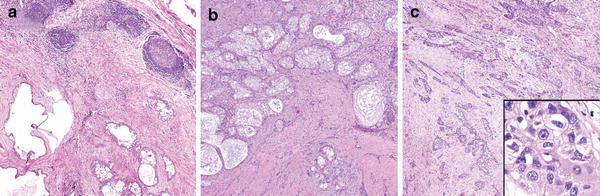

Grading of adenoid cystic carcinoma has been shown to be prognostically useful in several series [911]. Unlike many grading schemes, adenoid cystic carcinoma grading quick and simple in that it is based solely on growth pattern. As early as 1958, Patey and Thackray [12] noted that a solid growth pattern imparts a poor prognosis. Subsequently, grading of this tumor has evolved into stratification into three grades of increasing aggressiveness based on predominant growth pattern: [10, 11] grade 1: tubular, grade 2: cribriform, grade 3: solid (Fig. 2). Generally, a tumor with a greater than 30% solid component belongs in the ‘grade 3’ category. However, it is suggested that any solid component imparts a poor prognosis, and that the relationship between solid growth pattern percentage and prognosis is somewhat linear and that assigning a cut-off may be arbitrary. The current WHO classification refers to tumors by predominant pattern rather than actually assigning a numeric grade.

Fig. 2

The various patterns/grades of adenoid cystic carcinoma. a Tubular, b cribriform, c solid. All grades are cytologically monomorphic and retain small dark angulated nuclear features